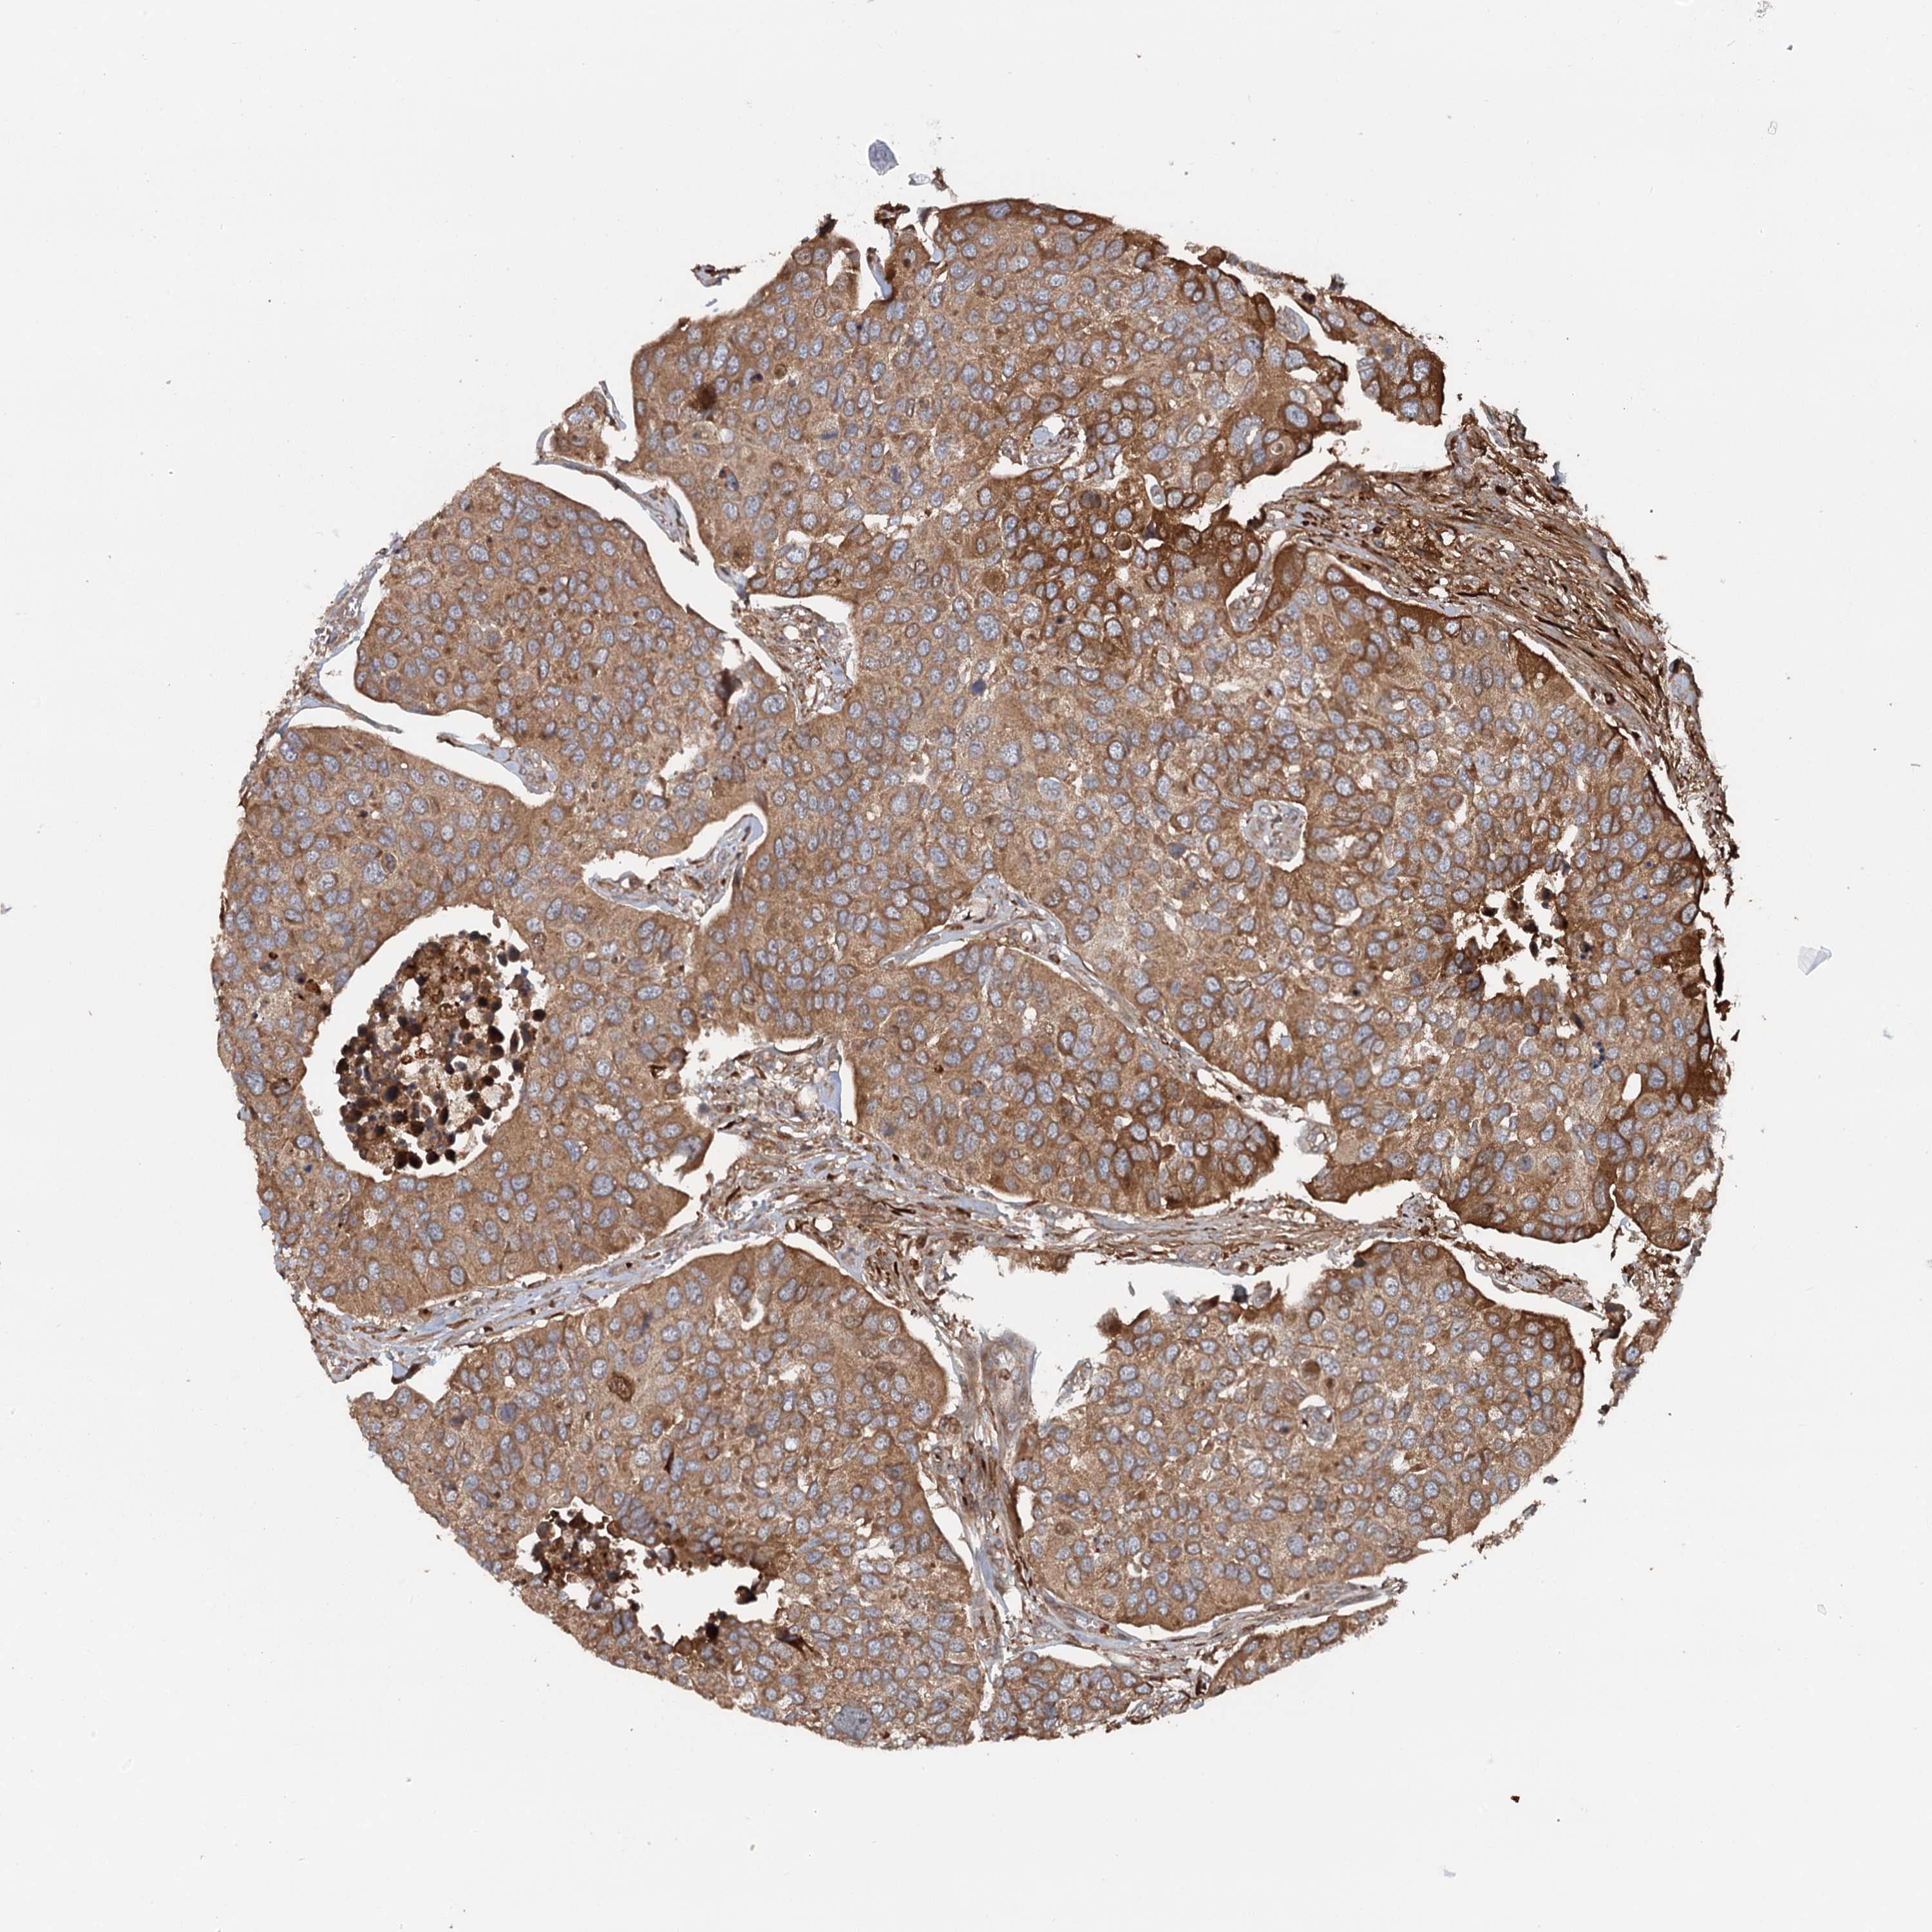

UROTHELIAL CANCER - Protein expressioni

A mouse-over function shows sample information and annotation data. Click on an image to view it in a full screen mode. Samples can be filtered based on level of antibody staining by selecting one or several of the following categories: high, medium, low and not detected. The assay and annotation is described here.

Note that samples used for immunohistochemistry by the Human Protein Atlas do not correspond to samples in the TCGA dataset.

Antibody stainingi

Antibody staining in the annotated cell types in the current human tissue is reported as not detected, low, medium, or high, based on conventional immunohistochemistry profiling in selected tissues. This score is based on the combination of the staining intensity and fraction of stained cells.

Each image is clickable and will lead to virtual microscopy that enables deeper exploration of all samples and also displays staining intensity scores, fraction scores and subcellular localization as well as patient and tissue information for each sample.

Antibody HPA038576

Antibody HPA038577

Staining

High

Medium

Low

Not detected

Intensity

Strong

Moderate

Weak

Negative

Quantity

>75%

75%-25%

<25%

None

Location

Nuclear

Cytoplasmic/membranous

Cytoplasmic/membranous,nuclear

Urothelial carcinoma, High grade

Urothelial carcinoma, Low grade

Urothelial carcinoma, NOS